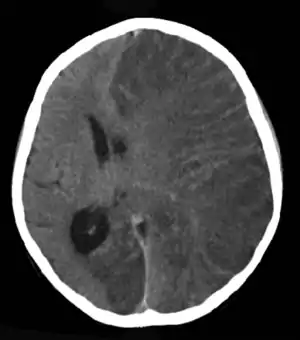

| Brain CT scan of a girl with Rasmussen's encephalitis. | |